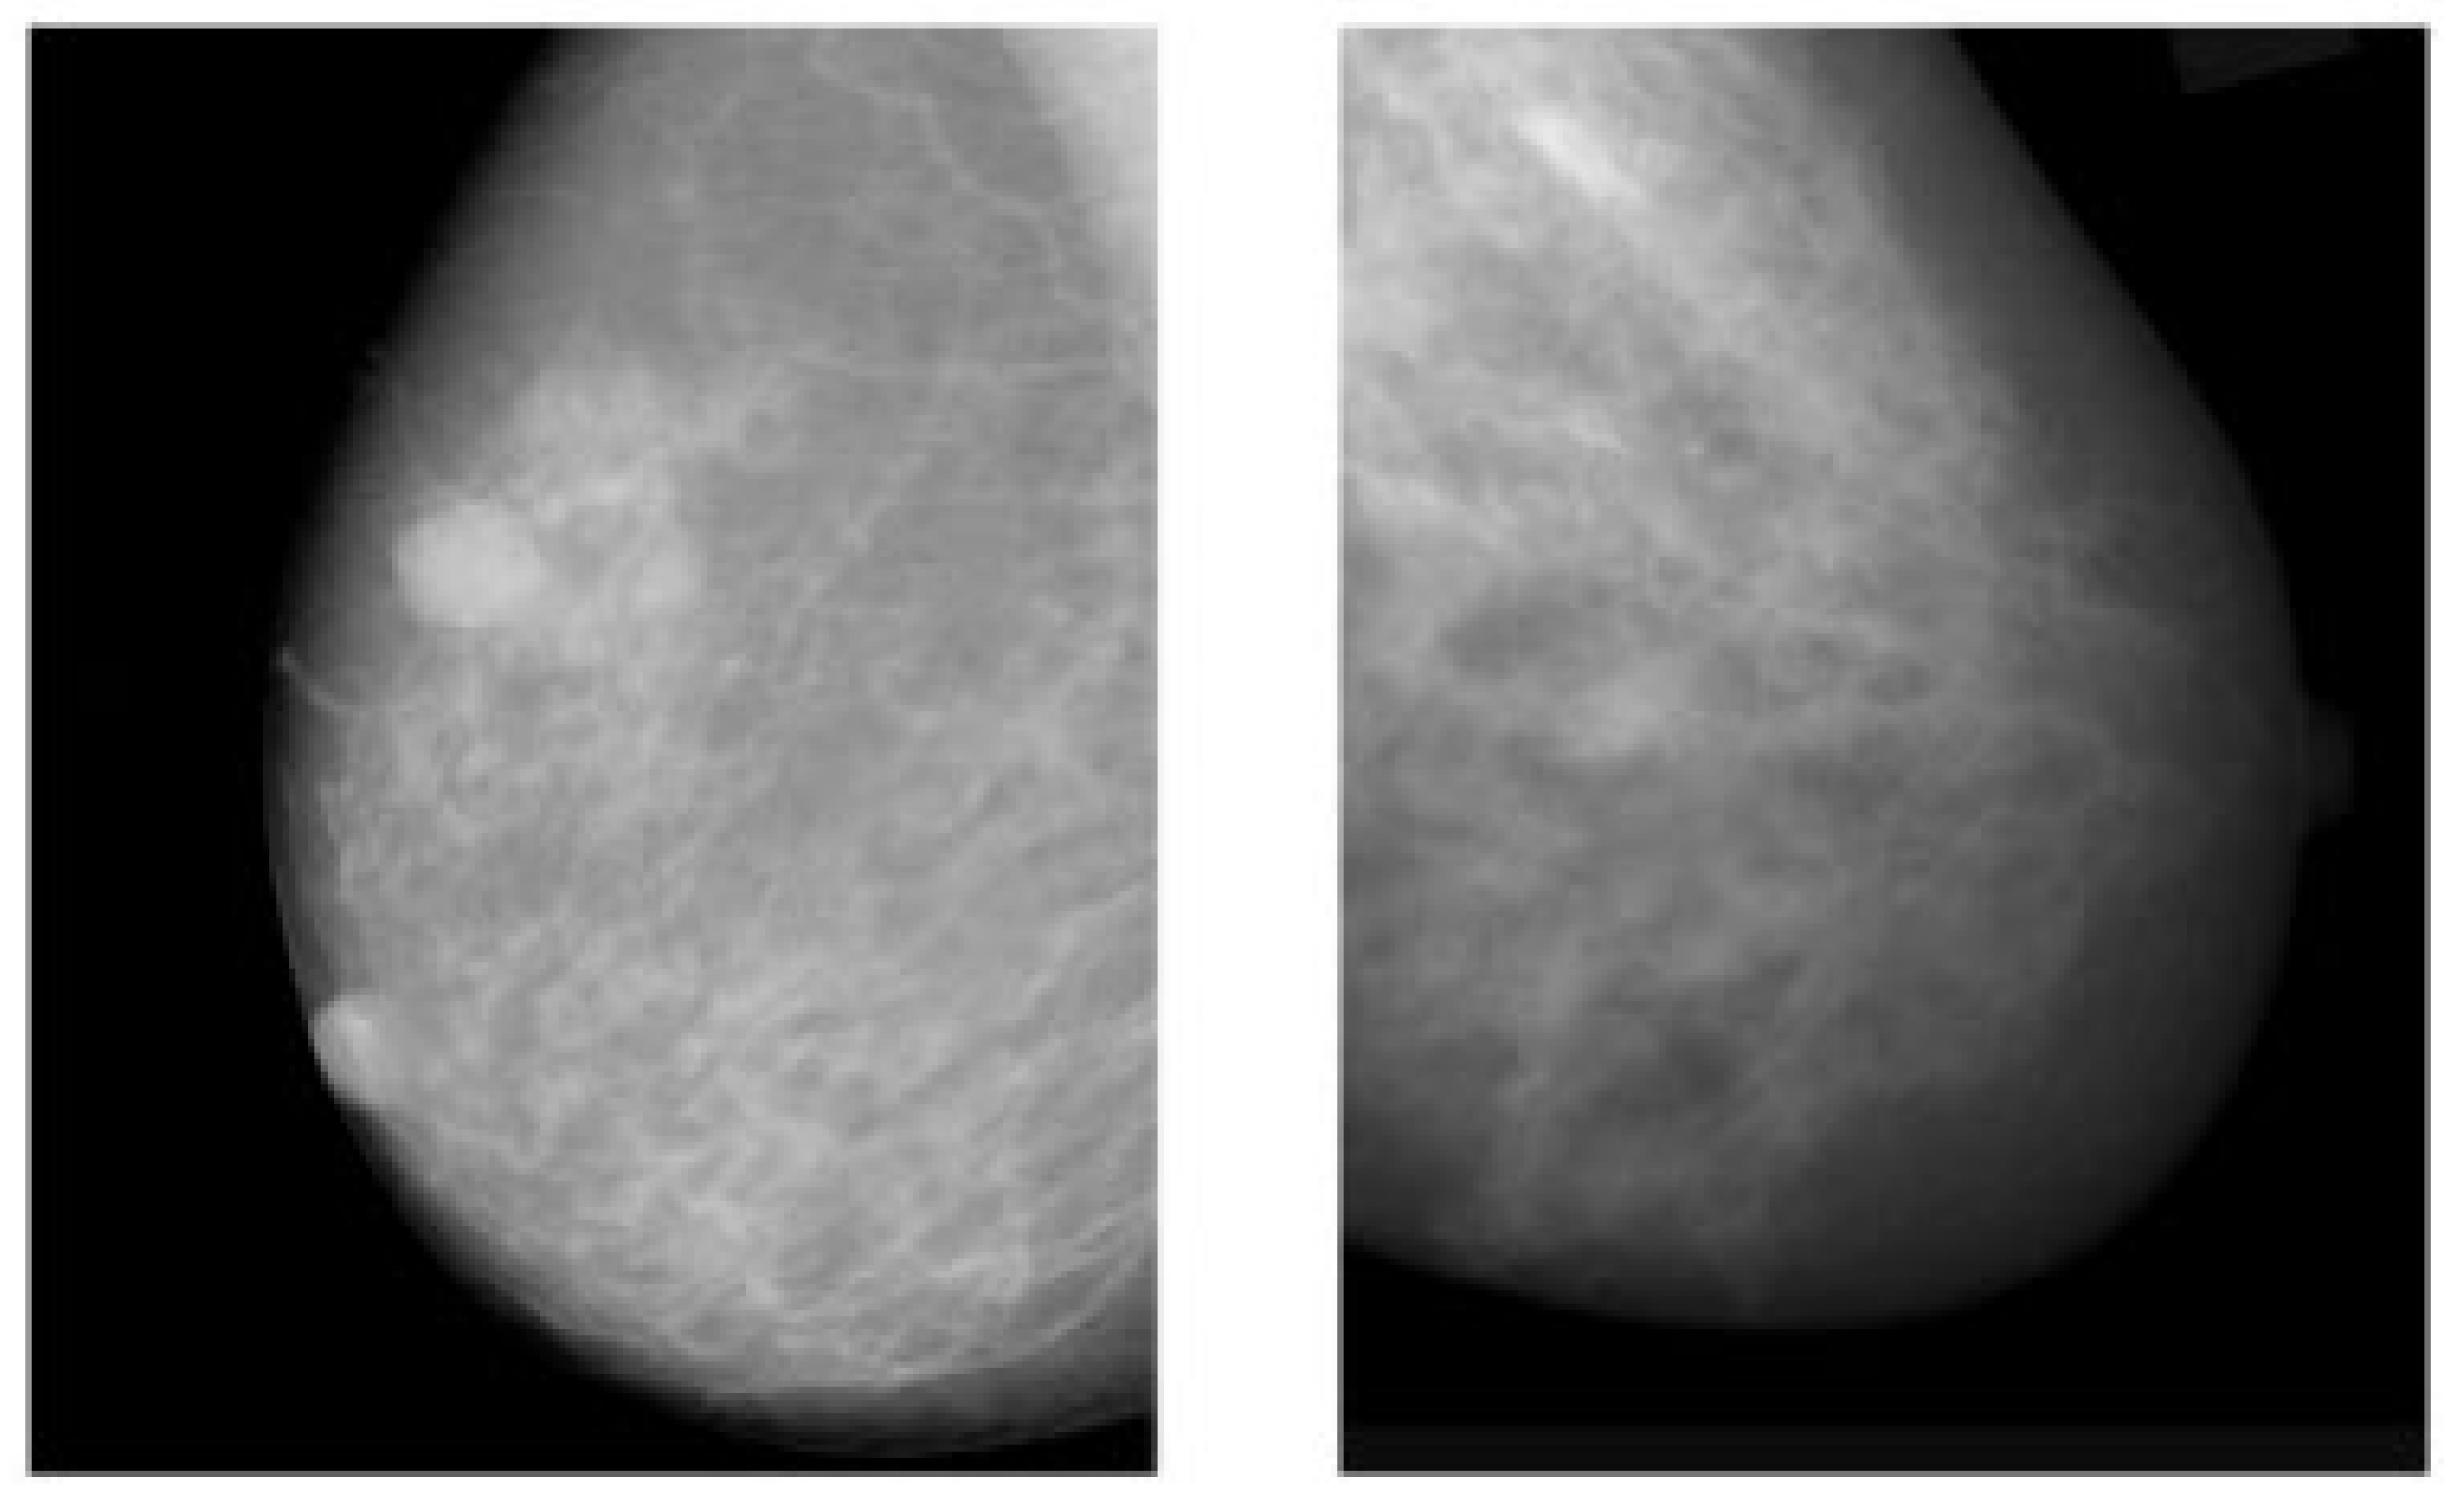

The advantages of mammograms, such as being cost-effective to detect tumors in the initial stage before development, mean that MMs are the most promising imaging screening technique in clinical practice. MMs are generally images of breasts produced by low-intensity X-rays (Figure 1) [33]. In this imaging modality, cancerous regions are brighter and more clear than other parts of breast tissue, helping to detect small variations in the composition of the tissues; therefore, it is used for the diagnosis and analysis of breast cancer [34,35] (Figure 1). Although MMs are the standard approach for breast cancer analysis, it is an inappropriate imaging modality for women with dense breasts [36], since the performance of MMs highly depends on specific tumor morphological characteristics [36,37]. To deal with this problem, using automated whole breast ultrasound (AWBU) or other methods are suggested with MMs to produce a more detailed image of breast tissues [38].

Figure 1.

Example of breast cancer images using traditional film MMs. Reprinted/adapted with permission from [49]. 2021, Elsevier.